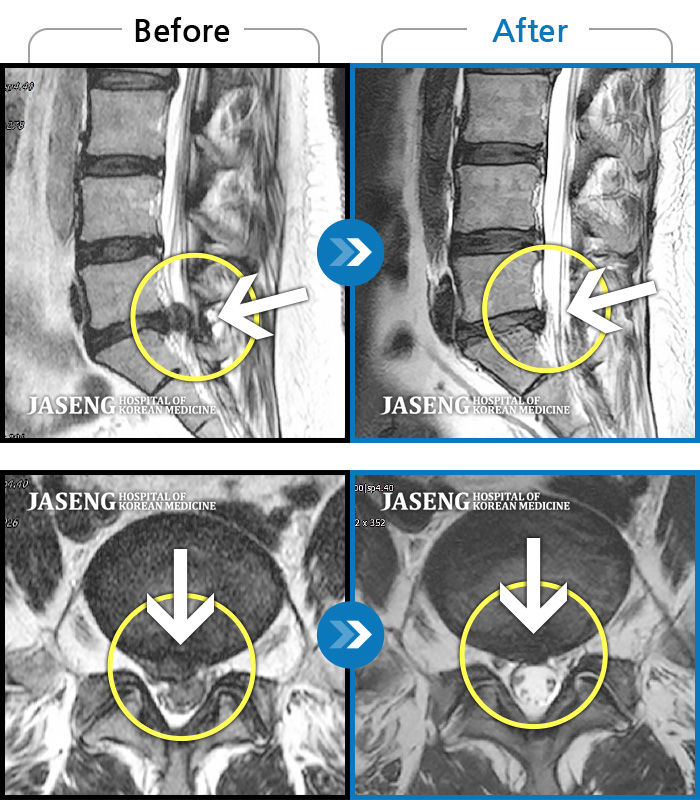

허리디스크

도움받은 사례

강남 · 강만호 원장

허리통증이 심해서 숙이기 어렵고 차에서 내리기 힘들었습니다.

촬영시기

2021.01.06 ~ 2025.03.10

2025.03.20

조회수 13,018